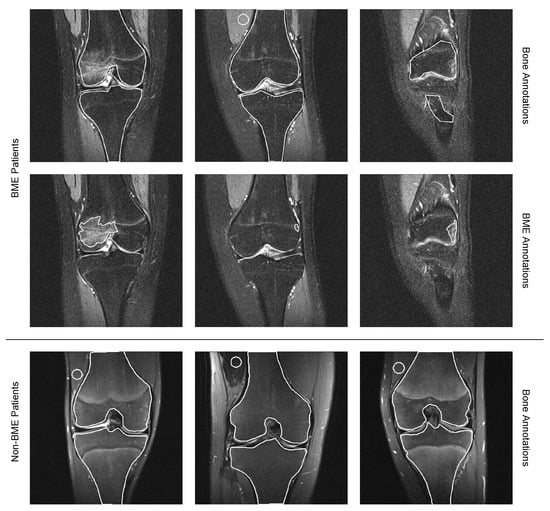

| # Slices with Bones Segmented | # Patients | |||

|---|---|---|---|---|

| With Edema Regions | Without Edema Regions | Total Slices | Total Patients | |

| Edema Patients | 228 | 85 | 313 | 28 |

| Non-Edema Patients | - | 36 | 36 | 36 |